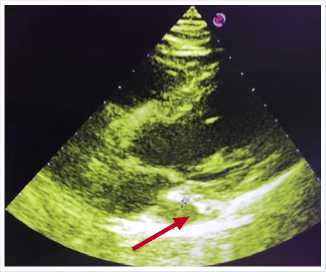

По данным ультразвукового исследования сердца: устье верхней полой вены в типичном месте не лоцируется; коронарный синус расширен до 18 мм. Ультразвуковые признаки персистирующей левой верхней полой вены (возможно единственной) (Рис. 3).

Рис. 3. Ультразвуковая сканограмма сердца. Стрелочкой показан расширенный коронарный синус.